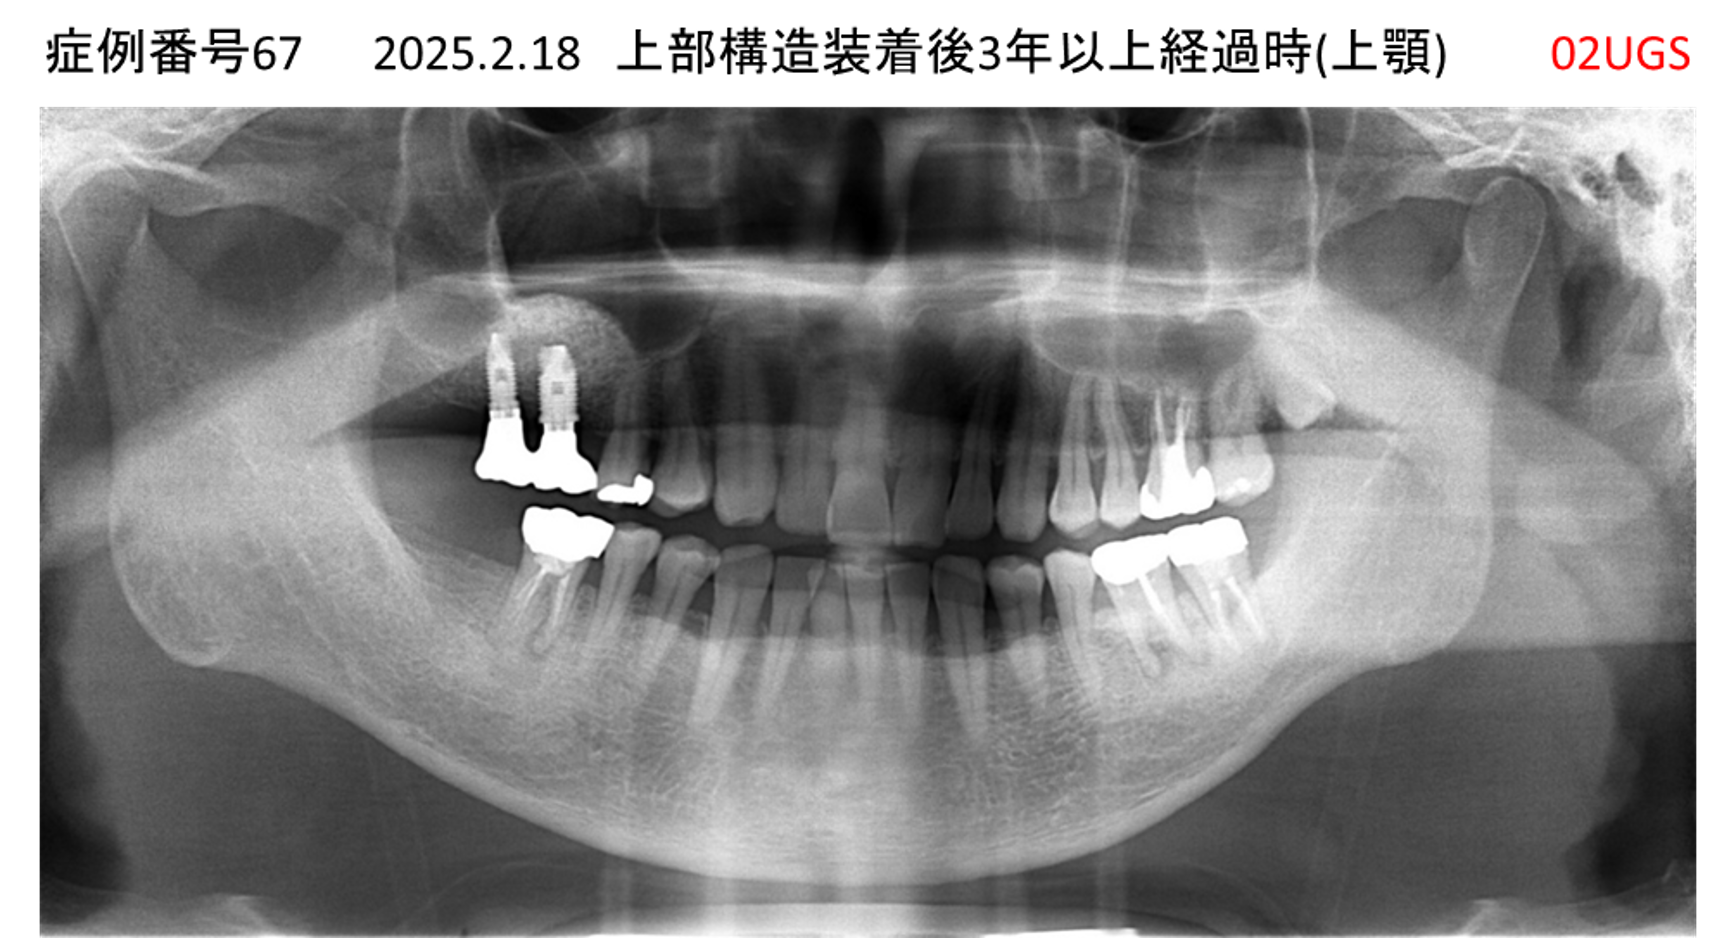

上の前歯が揺れていて痛い患者様のインプラント症例

| 患者さんの症状(主訴) |

上の前歯が揺れていて痛い |

| 治療内容 |

抜歯即時インプラント |

| 治療結果 |

痛みがなく、しっかり噛める。 見栄えがとても良い |

| 治療の注意点(リスク/副作用) |

インプラントが壊れたら再治療が必要 |